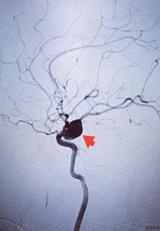

近日,家住大丰区新丰镇季某某,女,59岁,既往有“高血压、糖尿病”史3年多,一直自行服药治疗,清晨8点多在家时突发剧烈头痛,随后意识模糊不清,被家人发现后报120紧急送到我院急诊室行头颅CT检查示:蛛网膜下腔出血。随即启动卒中绿色通道,神经外科副主任医师沈华第一时间到达急诊室,仔细查看病人并分析病情:自发...2023-05-09